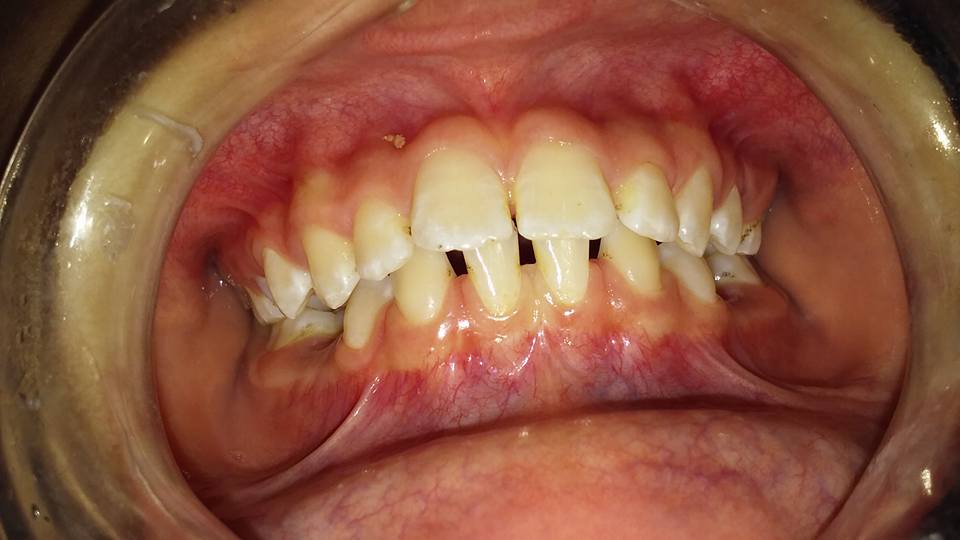

Nuestra misión es solucionar diferentes tipos de dolencias y/o problemas, tales como: caries, restauraciones, bruxismo, exodoncia, encías (gingivitis y/o periodontitis), ortodoncia, endodoncia y reposición de piezas dentarias.

Trabajamos con adultos y adolescentes desde 12 años. Atendemos a particulares.

HIGIENE Y ESTÉTICA BUCAL